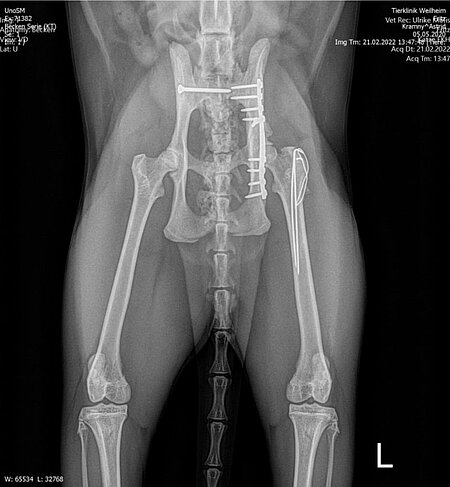

Röntgenbilder mit freundlicher Genehmigung Tierklinik Weilheim.

Bei der Nachuntersuchung des Patienten sechs Monate später präsentierte sich der Kater völlig beschwerdefrei und war sowohl in der Beckenregion als auch an den Gliedmaßen kräftig bemuskelt. Die Knochenbrüche waren sehr gut geheilt, ohne Einengung der Beckenhöhle und ohne die Ausbildung einer Hüftgelenksarthrose. Von einer Entfernung der Implantate wurde abgesehen, da alle Metallteile reizlos und ohne Lageveränderung integriert waren.